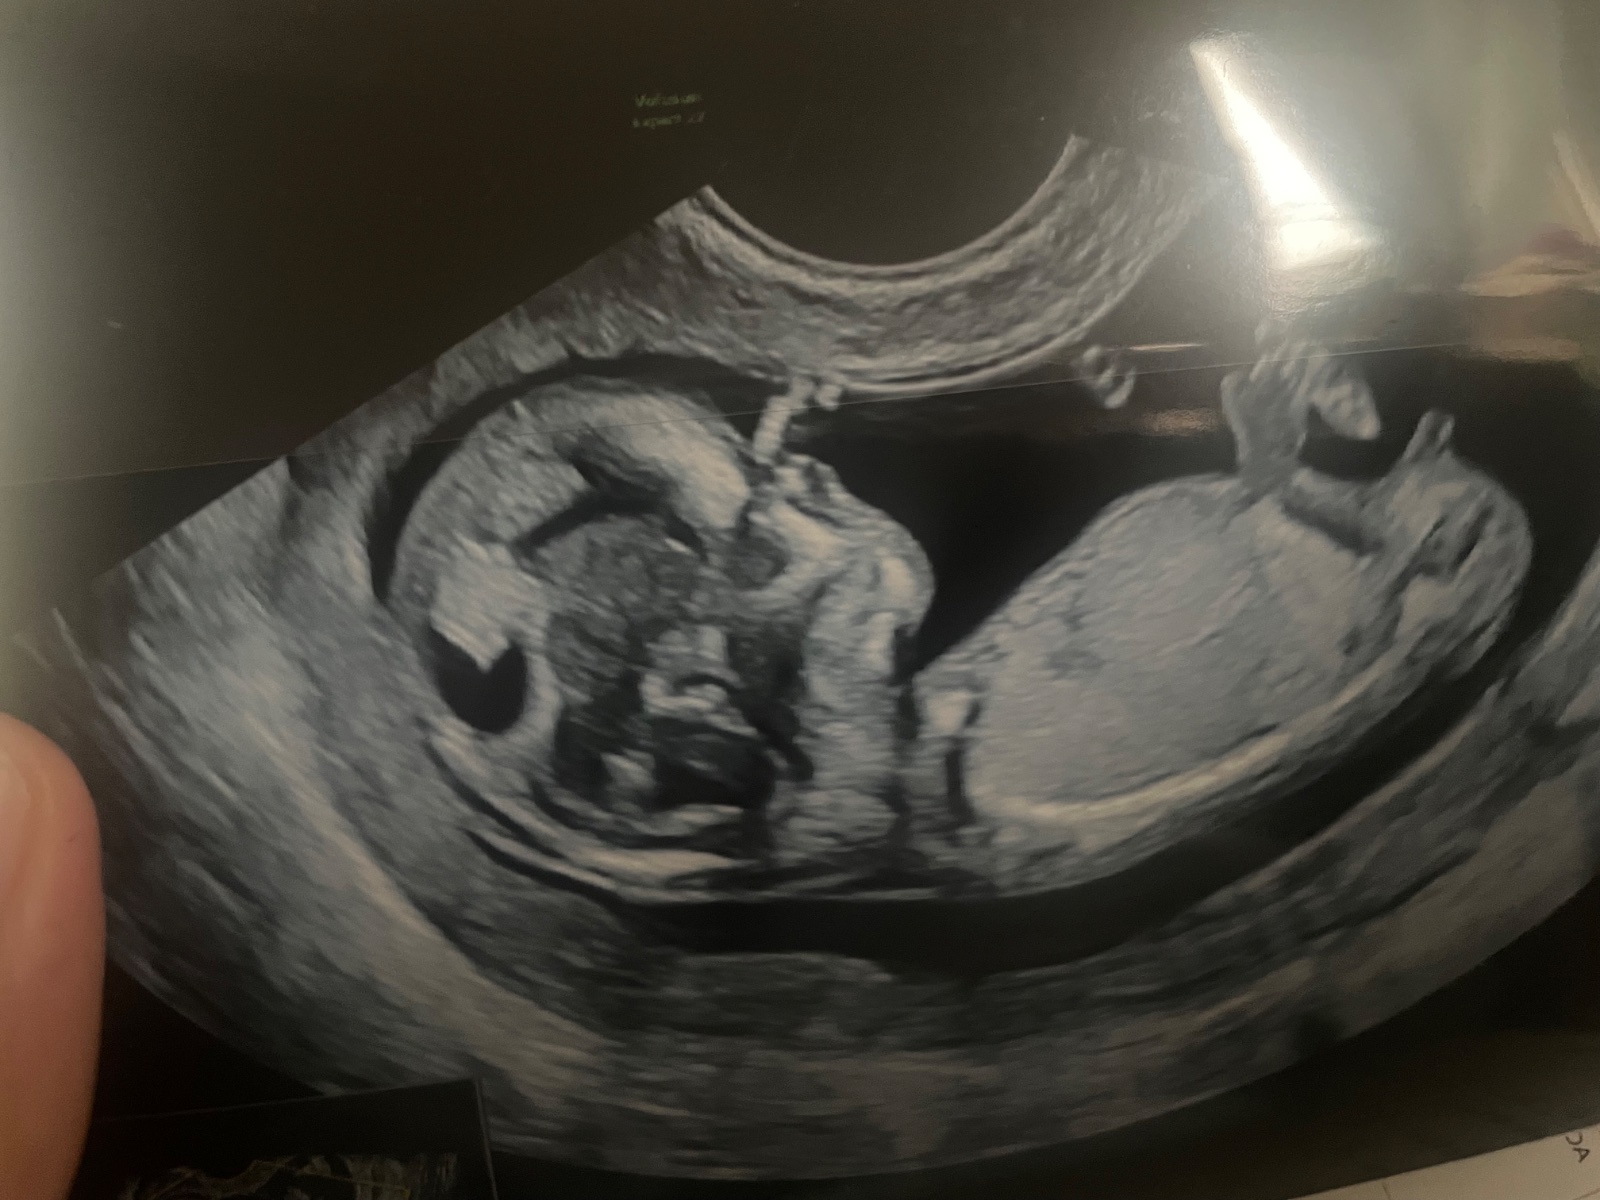

Prosim, setkal se tu někdo na prvním screeningu s vadou obličeje? Lékařka řekla, že se jí zda malé čelo a propadlý obličej :( že celý obličej je nějaký propadlý, nosní kůstka přítomna. Rizika syndromů se nepotvrdila. MUDr se ptala, zda nemáme v rodině genetické vady obličeje, ale to opravdu nemáme. Vubec nevim na co se připravit :(

@reeeza tak dneska kontrola, paní primářka řekla, že žádné anomálie v obličeji nevidí, screening negativní, všechno v pořádku 🥺🩵